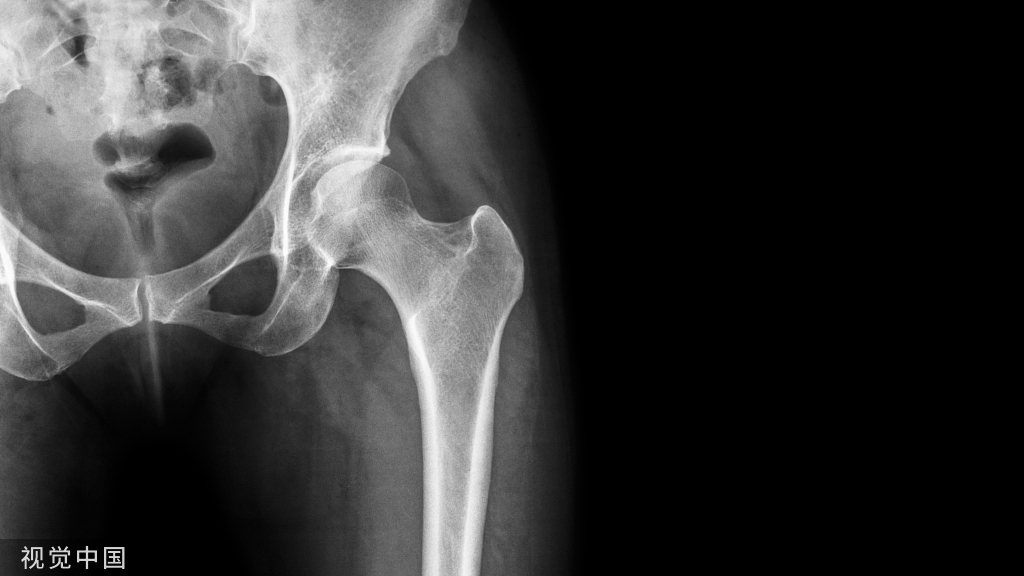

股前外侧穿支皮瓣(ALTP,徐达传 1984年 )

CASE 股前外侧穿支皮瓣